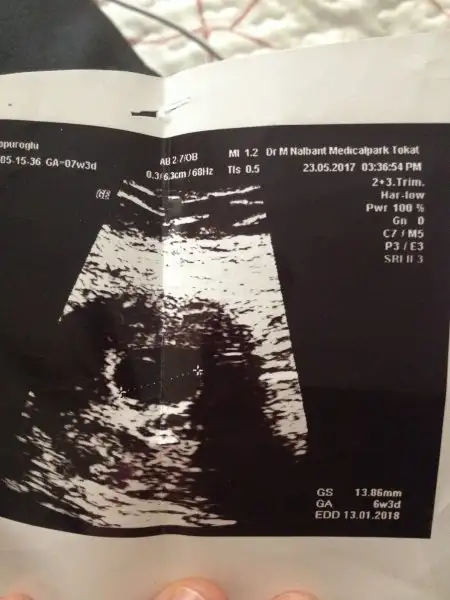

Bu da cuma gunununki ama bu uzaktan çekilmiş yakınlaştırmams doktr

esra bence bu gec dollenme cunku ilk usg de kese bes milim ikincide yaklasik 8 milim yanlis gormediusm.kalp durmasi olunca kese gelismez mantiken.bozulur ve kanamayla atilir.bulantin falan yoksa vile gogus agrin yani herhangi bir gebelik belirtin devam ediyorsa daha iyi bi dr a git bence ve bekleme.uni hastanesi varsa hatta aciline git

Arkadssn ddigi dogru Esr02 Esr02 bak benim kalp atisini duydugum gun 4.3 mm ertesi gun yani kalp atisi durdugu 5.4 mm kalms ve bozulmus sennkinde ole bisey kese gelisiyo bozulma vs. Bisey gorunmuyo

Aslında kese buyur ama çocuk içinde gelişmezse küçücük kalıyor